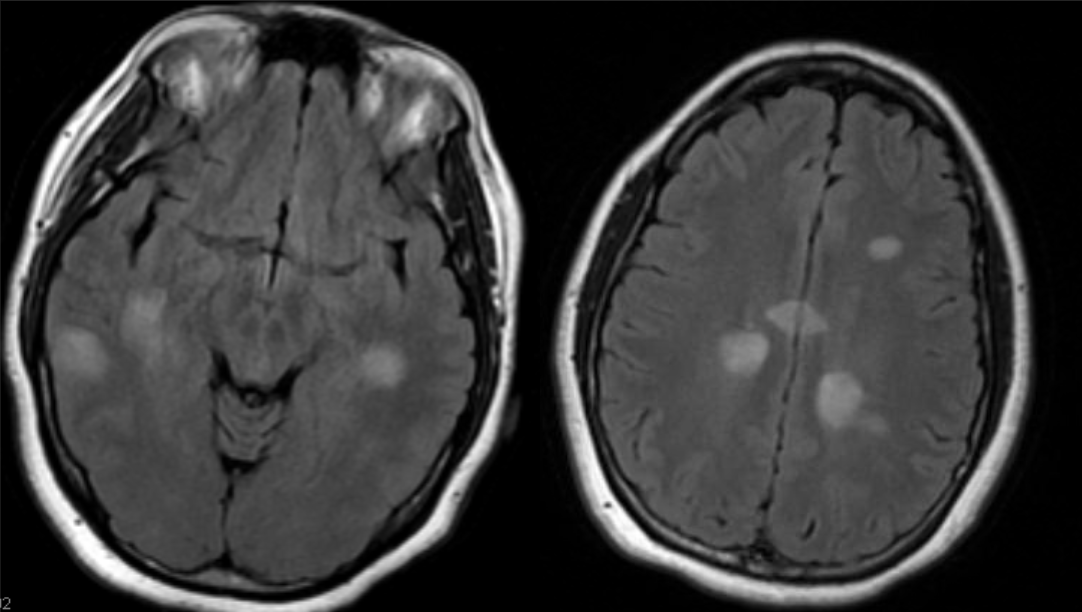

A 45 year-old male with MS developed cognitive slowing and abulia.

Progressive multifocal leukoencephalopathy (PML)

An 8 year-old child presented with encephalopathy and seizures.

Acute disseminated encephalomyelitis (ADEM)